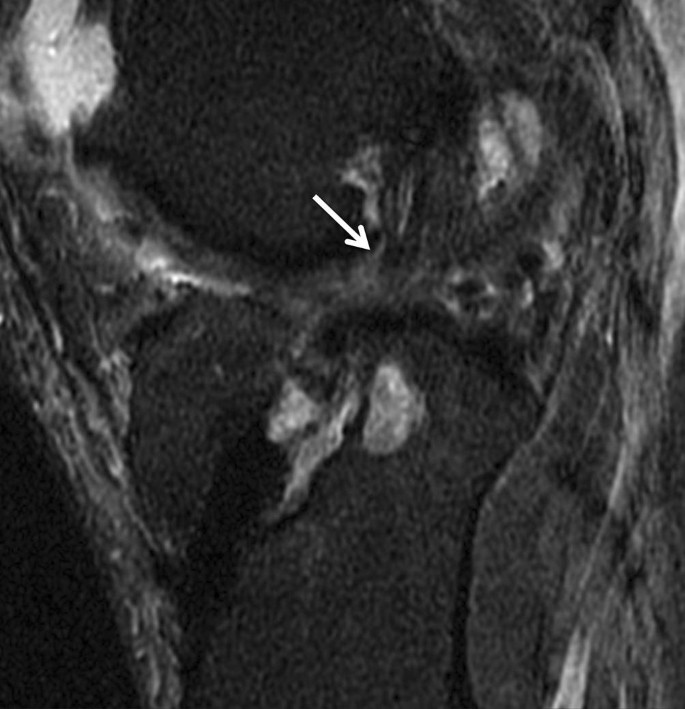

Partialrupturen können sich sowohl in einer Kaliberzunahme mit Signalintensitätserhöhung in T1- und T2-gewichteten Aufnahmen als auch in einer Ausdünnung der Sehne äußern (Abb. 7). Eine Elongation mit abgeflachtem Verlauf des Bands kann eines der Kriterien für die Partialruptur sein. Einer der Fallstricke für die Fehlinterpretation der Signaländerung ist die Synovialisation des Kreuzbandersatzes zwischen dem 3. und 12. postoperativen Monat. Die genaue Anamnese des Patienten mit der Information über den Zeitpunkt des Bandersatzes ist daher ausschlaggebend, um die Signalveränderung und Kaliberschwankung richtig einzuordnen.

Abb. 7

figure 7

Die sagittalen fettunterdrückten protonengewichteten Sequenzen zeigen eine deutliche Auftreibung und ein Ödem in der VKB(vorderes Kreuzband)-Plastik (Pfeil); eine komplette Diskontinuität liegt nicht vor. Eine Synovialisation kann ein ähnliches Erscheinungsbild erzeugen